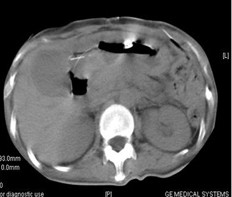

女,40歲,2006年10月底確診為胃腺癌(皮革胃),腹腔淋巴結(jié)轉(zhuǎn)移;2006年11月外科手術(shù)時(shí)見(jiàn)腹腔廣泛轉(zhuǎn)移(粘連),病灶無(wú)法切除(下圖1a,b),預(yù)期生存期低于3個(gè)月;留置(胃)造瘺管。2006年12月開(kāi)始今又生聯(lián)合化療治療,今又生2×1012VP,室溫下自行融化后加入到100ml生理鹽水中,30~40分鐘內(nèi)靜脈滴注完畢,1/次/周,連續(xù)使用6周。今又生給藥三天后靜脈化療。2007年7月外科手術(shù)拔除造瘺管;2007年9月隨訪,患者狀況良好,無(wú)復(fù)發(fā)。

2a 治療前 主動(dòng)脈前方,胃底和脾門(mén)之間見(jiàn)大量結(jié)節(jié)狀淋巴結(jié)

2b 治療后 主動(dòng)脈前方,胃底和脾門(mén)之間淋巴結(jié)大部分消失縮小,脂肪間隙較前清晰